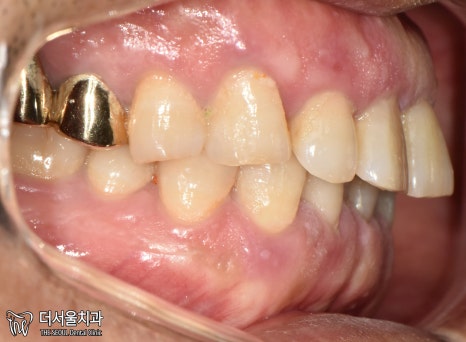

1. 구강 체크

현충일 공휴일 정상진료

서현역 치과를 찾아오셨던 환자분은

앞니와 왼쪽 끝 어금니에

이상 증세를 느껴 찾아오셨습니다.

겉으로 봤을 때는 큰 문제는 없는 것처럼 보입니다.

그럼 대체 무슨 문제가 있는 걸까요?

겉으로 보여지는 것이 아닌,

속을 들여봐야 알 수 잇겠네요.

엑스레이 촬영을 통해 체크해보겠습니다.